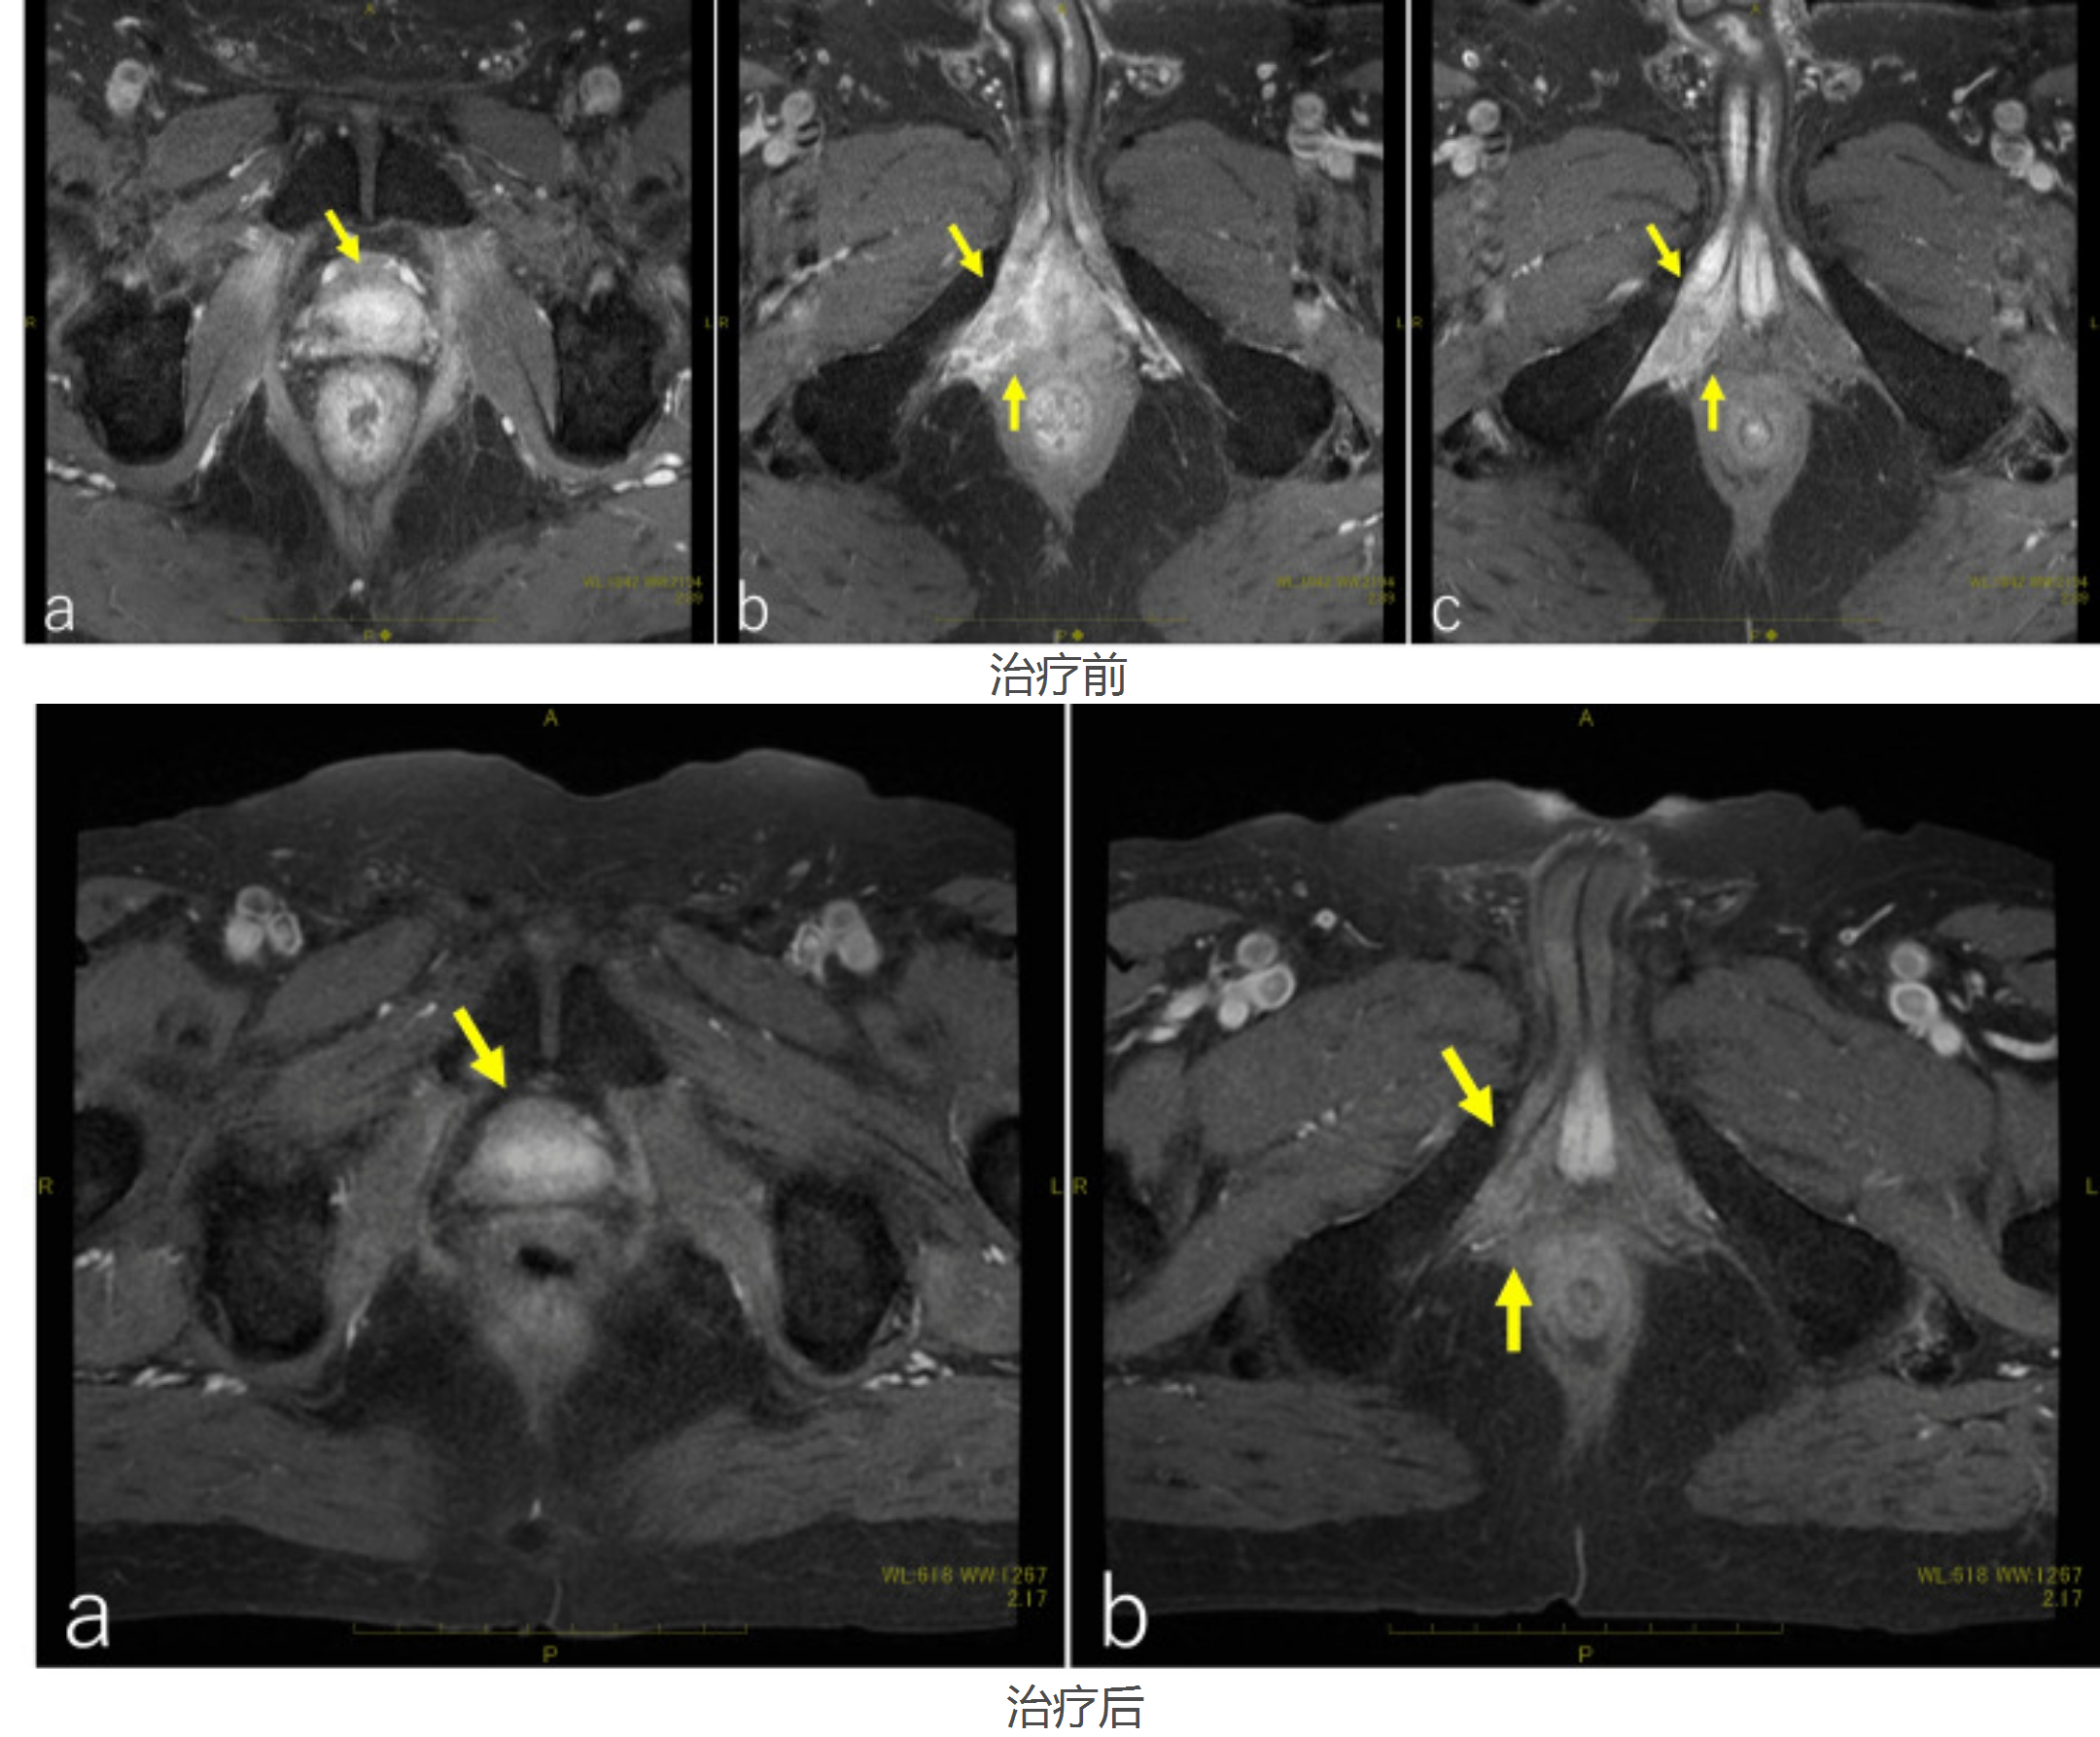

本文讲述一位拥有家族病史的患者,在经历前列腺癌术后生化复发后,如何通过寻求国际顶级医疗中心的第二诊疗意见,获得量身定制的精准治疗方案(质子治疗联合激素治疗),并最终重获新生的真实故事。他的经历凸显了高危人群早期筛查、复杂病例多学科诊疗以及前沿治疗技术的重要性。 当45岁的乔迪·富勒(Jody Fuller )拿到...

12月3日,MD安德森癌症中心分享了一个尖端质子治疗的成功案例,为全球复杂癌症患者带来新的希望。

当癌症患者挣扎于当前普通放射治疗方式带来的副作用时,是否期待着有一个治疗更加精准、副作用更低的先进治疗方式来帮助他们减缓痛苦?接下来,康和源免疫之家通过介绍一个故事,来带大家了解一款前沿的精确治疗技术-质子治疗。